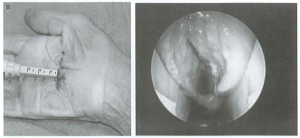

- Cắt TCL dưới quan sát camera

TCL đã cắt 1 phần và hoàn toàn